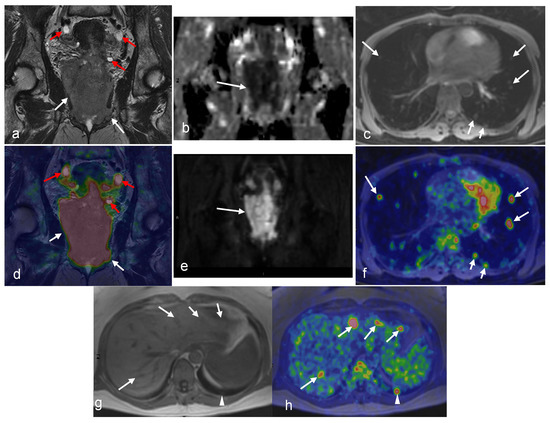

3.1. Cervical Cancer

3.2. Endometrial Cancer

3.3. Ovarian Cancer